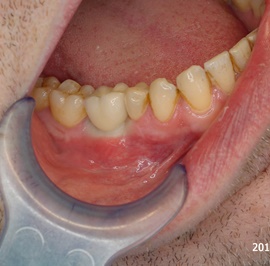

Pacjentka lat 41, odbudowa protetyczna zębów 24, 25 na implantach - korony porcelanowe na metalu. Po stronie prawej zdjęto most 13 - 16, poprawiono warunki kostne wyrostka zębodołowego i wykonano most na implantach od czwórki do szóstki, oraz nacementowano pojedynczą koronę na kła.

Pacjentka lat 50. Most od zęba 24 do zęba 27. Pękł korzeń zęba filarowego 24. Po ekstrakcji wykonano zabieg odbudowy kości wyrostka zębodołowego i podniesiono zatokę. Następnie po skorygowaniu kształtu i objętości dziąsła przytwierdzonego wykonano pojedyńcze korony na implantach 24, 26, oraz most 13-17